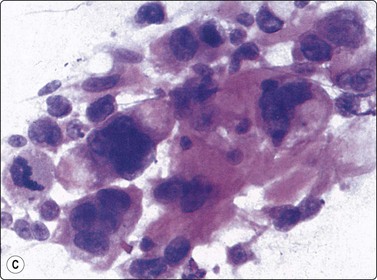

In atypical ES and PNET the cellular and nuclear atypia is more marked than in conventional ES. Rosette-like structures are more common and the distinction between large light and small dark cells less obvious, especially in PNET, and cells with thin cytoplasmic processes as well as rhabdomyoblast-like cells are present (Fig. 16.32).

image image

Fig. 16.32 ES/PNET family of tumors

Distinction between large light and small dark cells less obvious in PNET than in conventional Ewing’s, and cells with thin cytoplasmic processes (A) and rhabdomyoblast-like cells (B) are present (A, MGG, HP; B, H&E, HP).